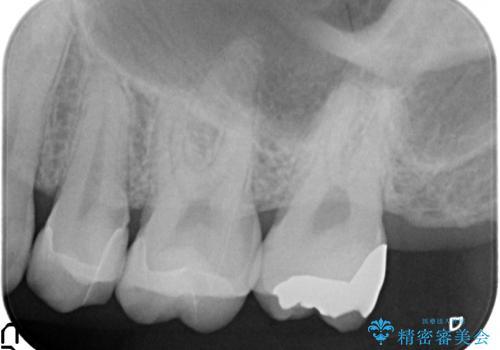

奥歯の詰め物のやりかえ セラミックインレー、ゴールドインレー

- 上の奥歯の詰め物が合っていないため、やりかえを行いました。

- 20万円 内訳 左上56:emaxインレー7万円x2 、左上7:PGAインレー6万円 (税別)費用は治療当時の料金となります

上の一番奥の歯は、一番目立たない場所なので(他人から見えない)、ゴールドインレーでも目立ちません。

セラミックインレーでは割れやすい大きさの虫歯または、歯が薄くなって被せなければいけないような場合でも、金属(ゴールド)は耐久性があり、クラウン(被せ物)にしなくて済みます。